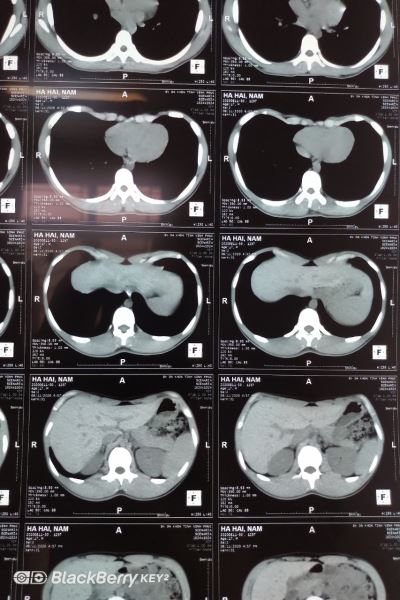

Hình ảnh dị dạng lồng ngực của N. trên phim CT |

Cậu bé Hà Hải N. (17 tuổi), bị biến dạng lồng ngực, ngực sập vào trong. Khi hoạt động thể lực mạnh khiến em cảm thấy khó thở và mệt nhiều. N. được gia đình đưa đến Bệnh viện Đa khoa tỉnh Vĩnh Phúc để khám. Qua thăm khám lâm sàng và chụp MSCT lồng ngực, người bệnh N. được chẩn đoán lõm đồng tâm nông, mức độ lõm nặng, chỉ số Haller (HI) ~ 4.2. (Đánh giá mức độ nặng bằng chỉ số Haller: HI bình thường 2.5, HI > 3.25 được xem như lõm ngực nặng). Từ đó, N. được bác sĩ chỉ định phẫu thuật nâng xương ức bằng phương pháp Nuss kết hợp nội soi.